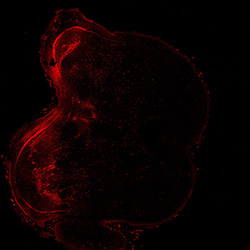

An anatomical analysis of the developing human midbrain from 6 post-conceptional weeks (PCW) to 22 PCW reveals increased tissue complexity, characterized by the emergence of dopaminergic nuclei, as highlighted by immunofluorescence analysis for tyrosine hydroxylase (TH).

TH

7PCW human midbrain